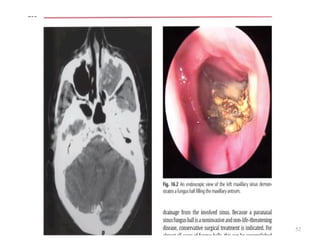

FUNGAL BALL

• Dense accumulation of fungus and the

associated debris presenting as a noninvasive

mass in the sinuses.

• Nasal obstruction , postnasal drip

• O/E - 40% - purulent discharge from the

involved sinus and 10% have polyps.

• CT SCAN

51

CT SCAN

• Single opacified sinus with a central area of

high attenuation is highly suggestive of fungus

ball

• Centrally within the involved sinus are areas of

hyperattenuation that correspond to fungal

debris and punctate calcifications.

• There is usually minimal or no sinus

expansion, but there may be a thick osteitic

bone reaction from the chronic state.